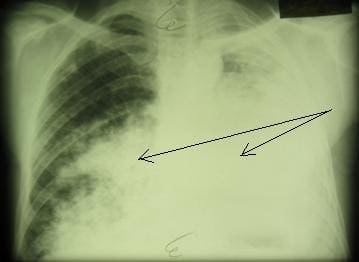

Полостная форма рака легкого: опухоль в правом легком указана стрелкой

Пневмониеподобная форма рака легкого с поражением обоих легких

с поражением нижней доли правого легкого